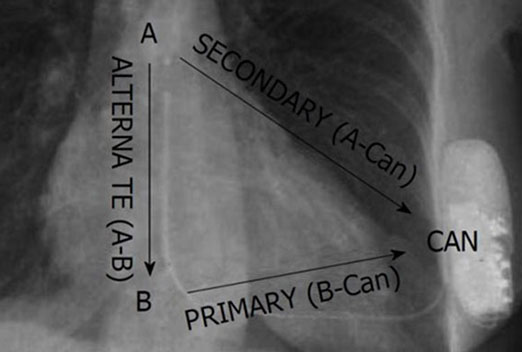

We have a some latest projects photos and Videos. this gallery explain different

health issues related to heart and more information for heart patients thats ill we help for your health improve.